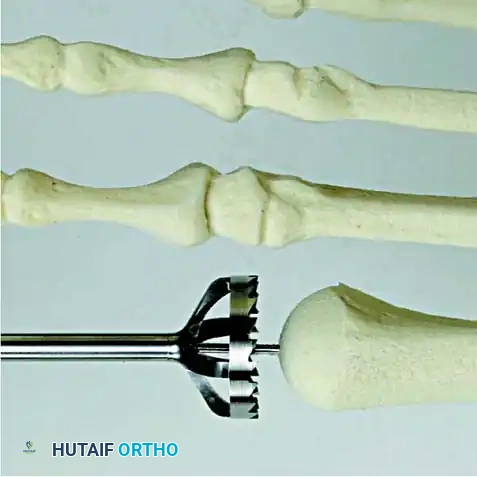

2. Joint Preparation: The capsule is incised, and the collateral ligaments are released. The severely eroded articular surfaces of the first metatarsal head and the base of the proximal phalanx are resected. Cup-and-cone reamers are highly recommended to preserve length while allowing multi-planar adjustment.

3. Positioning: The hallux is positioned in 10 to 15 degrees of valgus and 15 to 20 degrees of dorsiflexion relative to the first metatarsal shaft. Neutral rotation must be confirmed to ensure the toenail faces directly dorsal.

4. Fixation: Rigid internal fixation is achieved using a dorsal contoured titanium plate and a lag screw across the arthrodesis site.